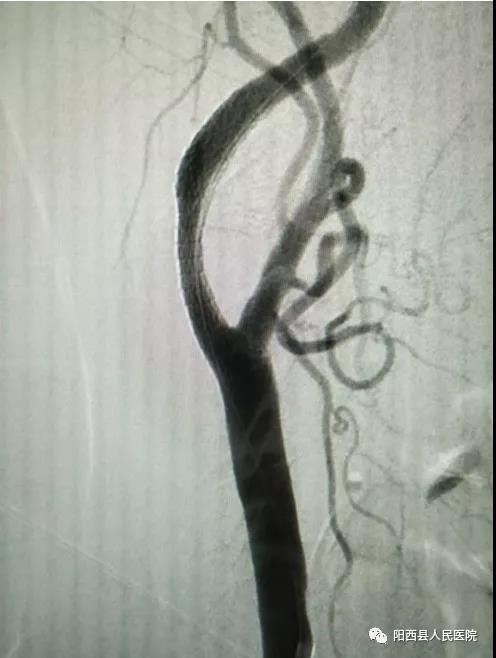

此次手术患者是一位84岁的老年男性,因左侧肢体乏力一天收住我院脑科中心。入院后完善各项常规检查,颅脑MRA示:右侧基底节区、放射冠脑埂塞。颈部血管彩超示:右侧颈内动脉起始段重度狭窄(狭窄》70%)。头颈部CTA示:右侧颈内动脉颈段混合性斑块,管腔中重度狭窄。排除禁忌后,进行DSA检查。术中发现RC1约60%症状性狭窄,在血管狭窄处放入支架1枚,患者血流情况恢复良好,左侧肢体肌力恢复,可自行行走。

DSA下支架植入影像